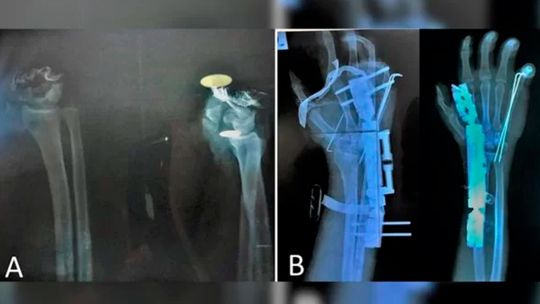

Médicos conseguem reimplantar mão totalmente decepada de jovem

Caso de jovem com mão decepada foi relatado em revista científica. Médicos deram detalhes do pré e pós cirurgia para reintegrar membro